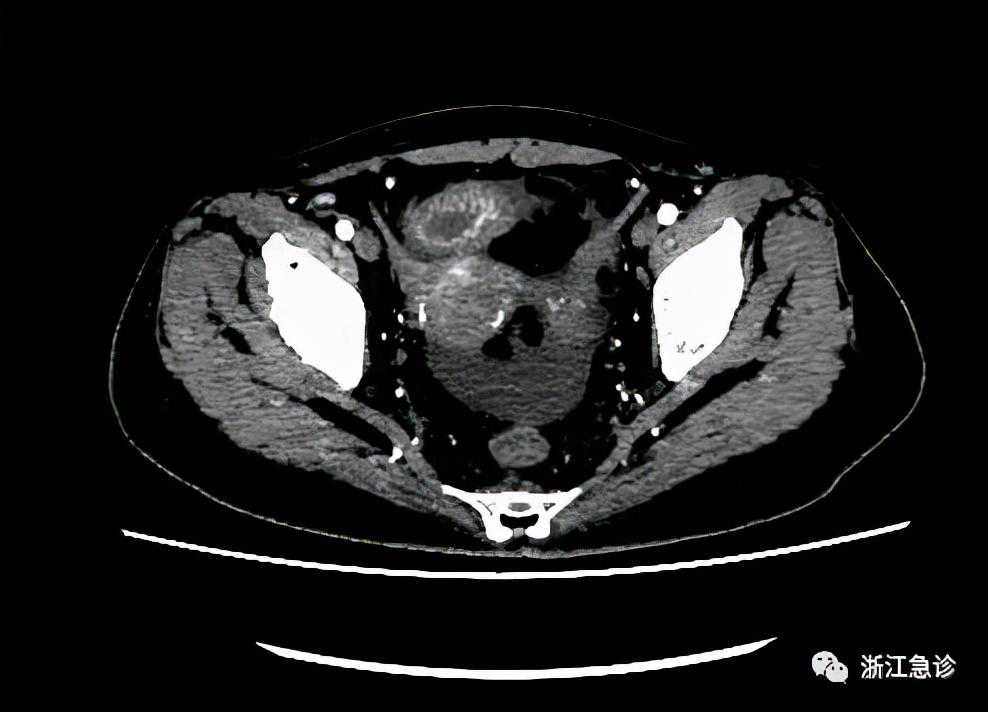

到我院后,又增做了肠系膜血管造影。除了有门静脉血栓外,还提示部分小肠肠壁水肿、增厚,肠系膜远端血管显示不清,缺血性改变,考虑“肠系膜上静脉血栓形成”。另外胸腔、腹腔及盆腔还有大量的积液,两肺有渗出性改变。

三个月后,呕吐突然加剧,并出现右下腹部疼痛加重,有时呕吐物带有血,实在熬不住了,只得急诊来院,复查“腹部肠系膜动脉CTA提示:1.结合病史,门脉血栓及肠系膜上静脉血栓治疗后,门脉海绵样变。2.小肠壁多发肿胀,考虑淤血性改变考虑;盆腹腔积液;肠系膜脂膜炎考虑。3.不均质脂肪肝”。还是没有其它发现。经过仔细比对前后CT,患者门静脉及脾静脉栓塞有了明显的改善,基本都通了。

到了第二次入院后的四十三天,复查“腹部肠系膜动脉CTA:1.结合病史,门脉血栓及肠系膜上静脉血栓治疗后,门脉海绵样变,请结合临床并随访。2.提示回盲肠区系膜炎性病变并盆腔积液,请结合临床。3.小肠梗阻。4.脂膜炎。5.不均质脂肪肝”。